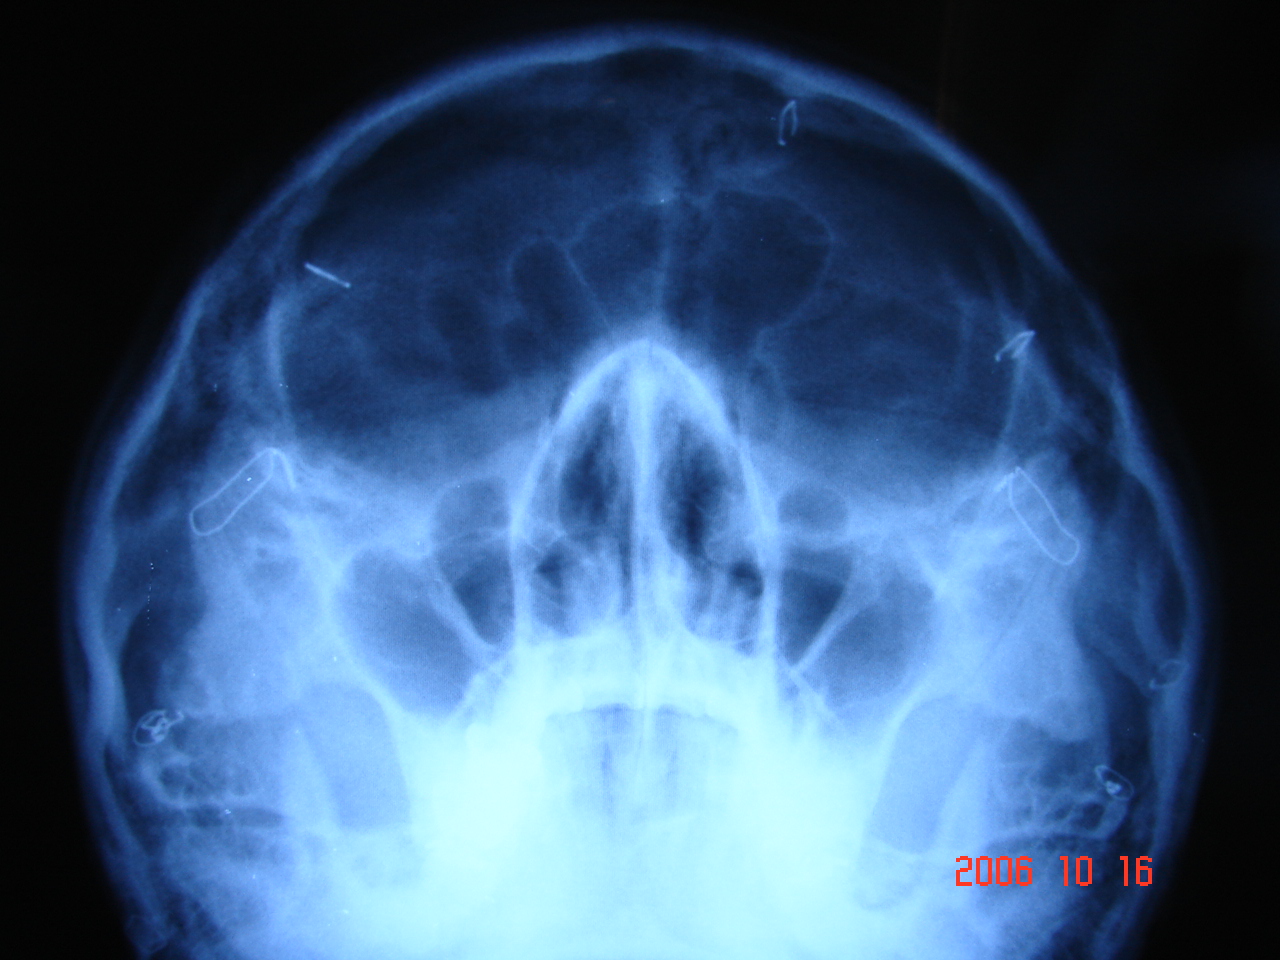

(설재윤성형외과)광대정면waters view 엑스레이 - 올바른 수술

(타병원)정면waters view엑스레이 - 부작용 수술

불유합-벌어짐,광대뼈 내려 앉음,계단현상-울퉁불퉁

1.절골 라인에서 광대뼈가 벌어져 유합되지 않는 상태

2.절골라인보다 밑으로 광대뼈가 내려앉은 상태

3.절골 라인에서 계단현상으로 광대뼈가 축소된 매끄럽지못한 울퉁불퉁 상태

단순 수술후기에 의지 말고 수술결과에 대해서 광대뼈 정면 waters view 나 광대측면 arch view로 객관적인 검사로 혹은 3ct 까지 수술내용을 검증 해 보겠다는 마음 가짐으로 수술을 결정하는것이 스스로 결정에 대해서 자기 몸에 책임을 질수 있는 행동입니다.

광대뼈 수술- 정면 waters view ,측면 arch view .